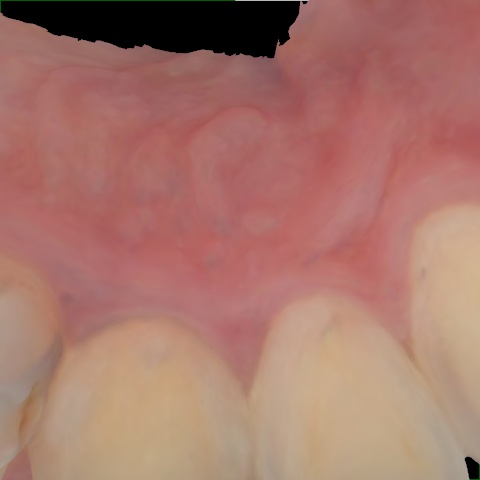

Annotated as "Good"